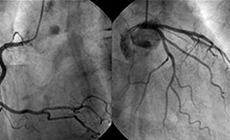

狭心症、心筋梗塞、末梢動脈疾患が疑われる患者さまがいらっしゃいましたら、循環器内科外来あてにご紹介ください。

循環器専門の医師が患者さまを診察し、適切な検査計画を検討させていただきます。